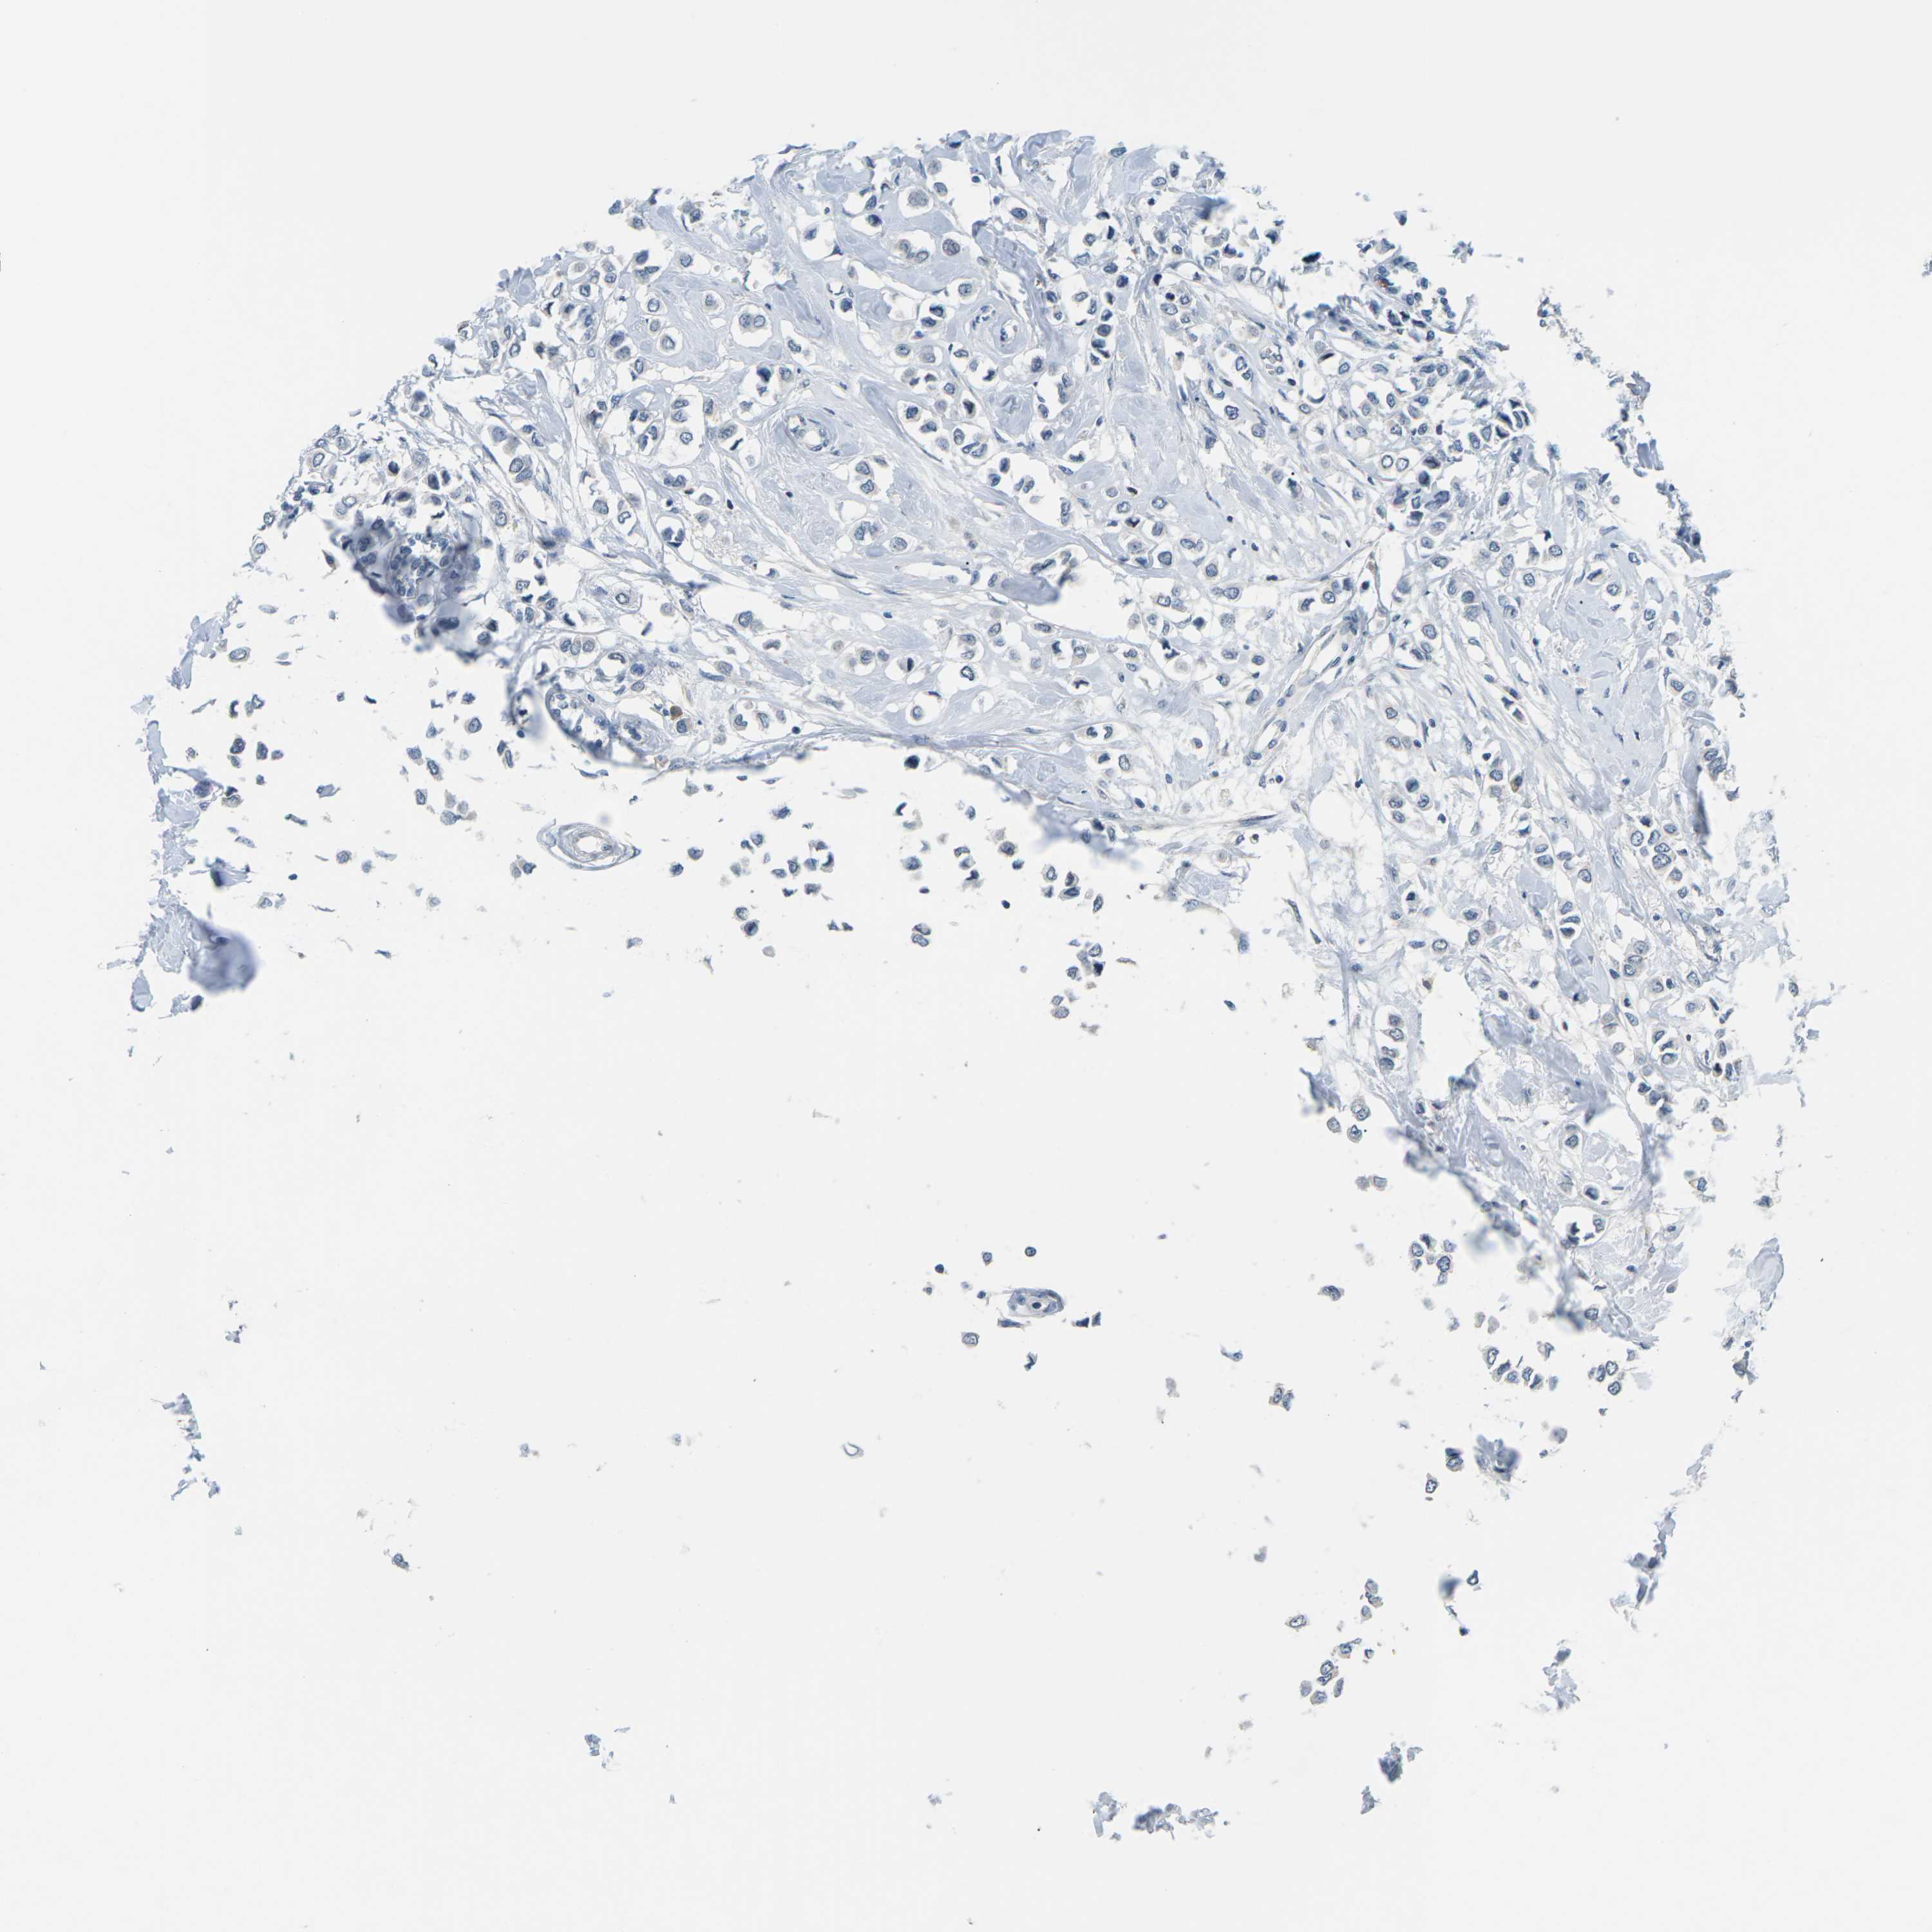

BRCA TCGA BRCA VALIDATION PROTEIN EXPRESSION